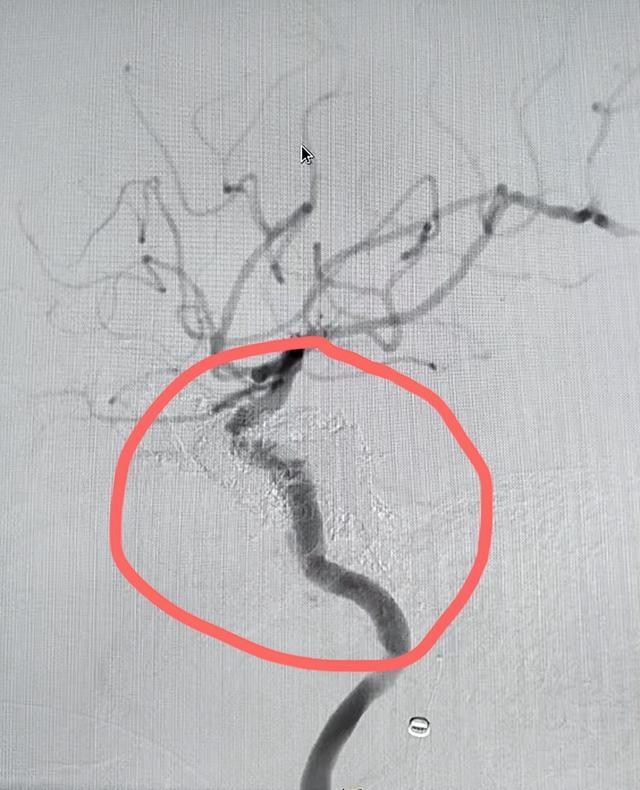

▲术后,海绵窦瘘消失

入院后进一步完善相关检查,邀请多学科会诊评估后,医疗团队为周先生制定了手术方案,并于2月18日由,康超文副主任医师团队为其施行颈内动脉海绵窦瘘弹簧圈栓塞术。手术历时3小时,成功将弹簧圈置入瘘口,有效阻断异常血流,恢复正常的血液循环。

术后,周先生的眼球逐渐回缩,视力恢复,头痛消失。